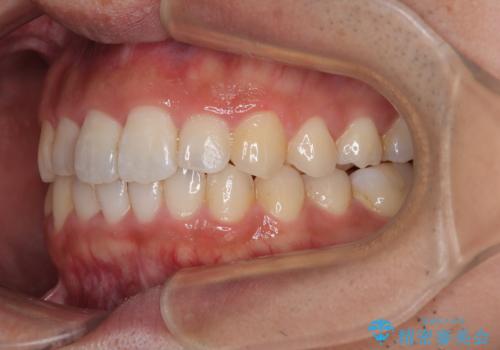

前歯のデコボコと突出感をマウスピース矯正できれいに

- 上下前歯のデコボコと突出感を気にして来院された患者様です。

目立たない装置を希望されたため、インビザラインによるマウスピース矯正を行うこととしました。

矯正治療後に銀歯をセラミックに替えたいとの要望があり、概ね歯列が整ったところで銀歯をセラミックに替え、仕上げにインビザライン1セットを使用して最終的に歯列を整えました。